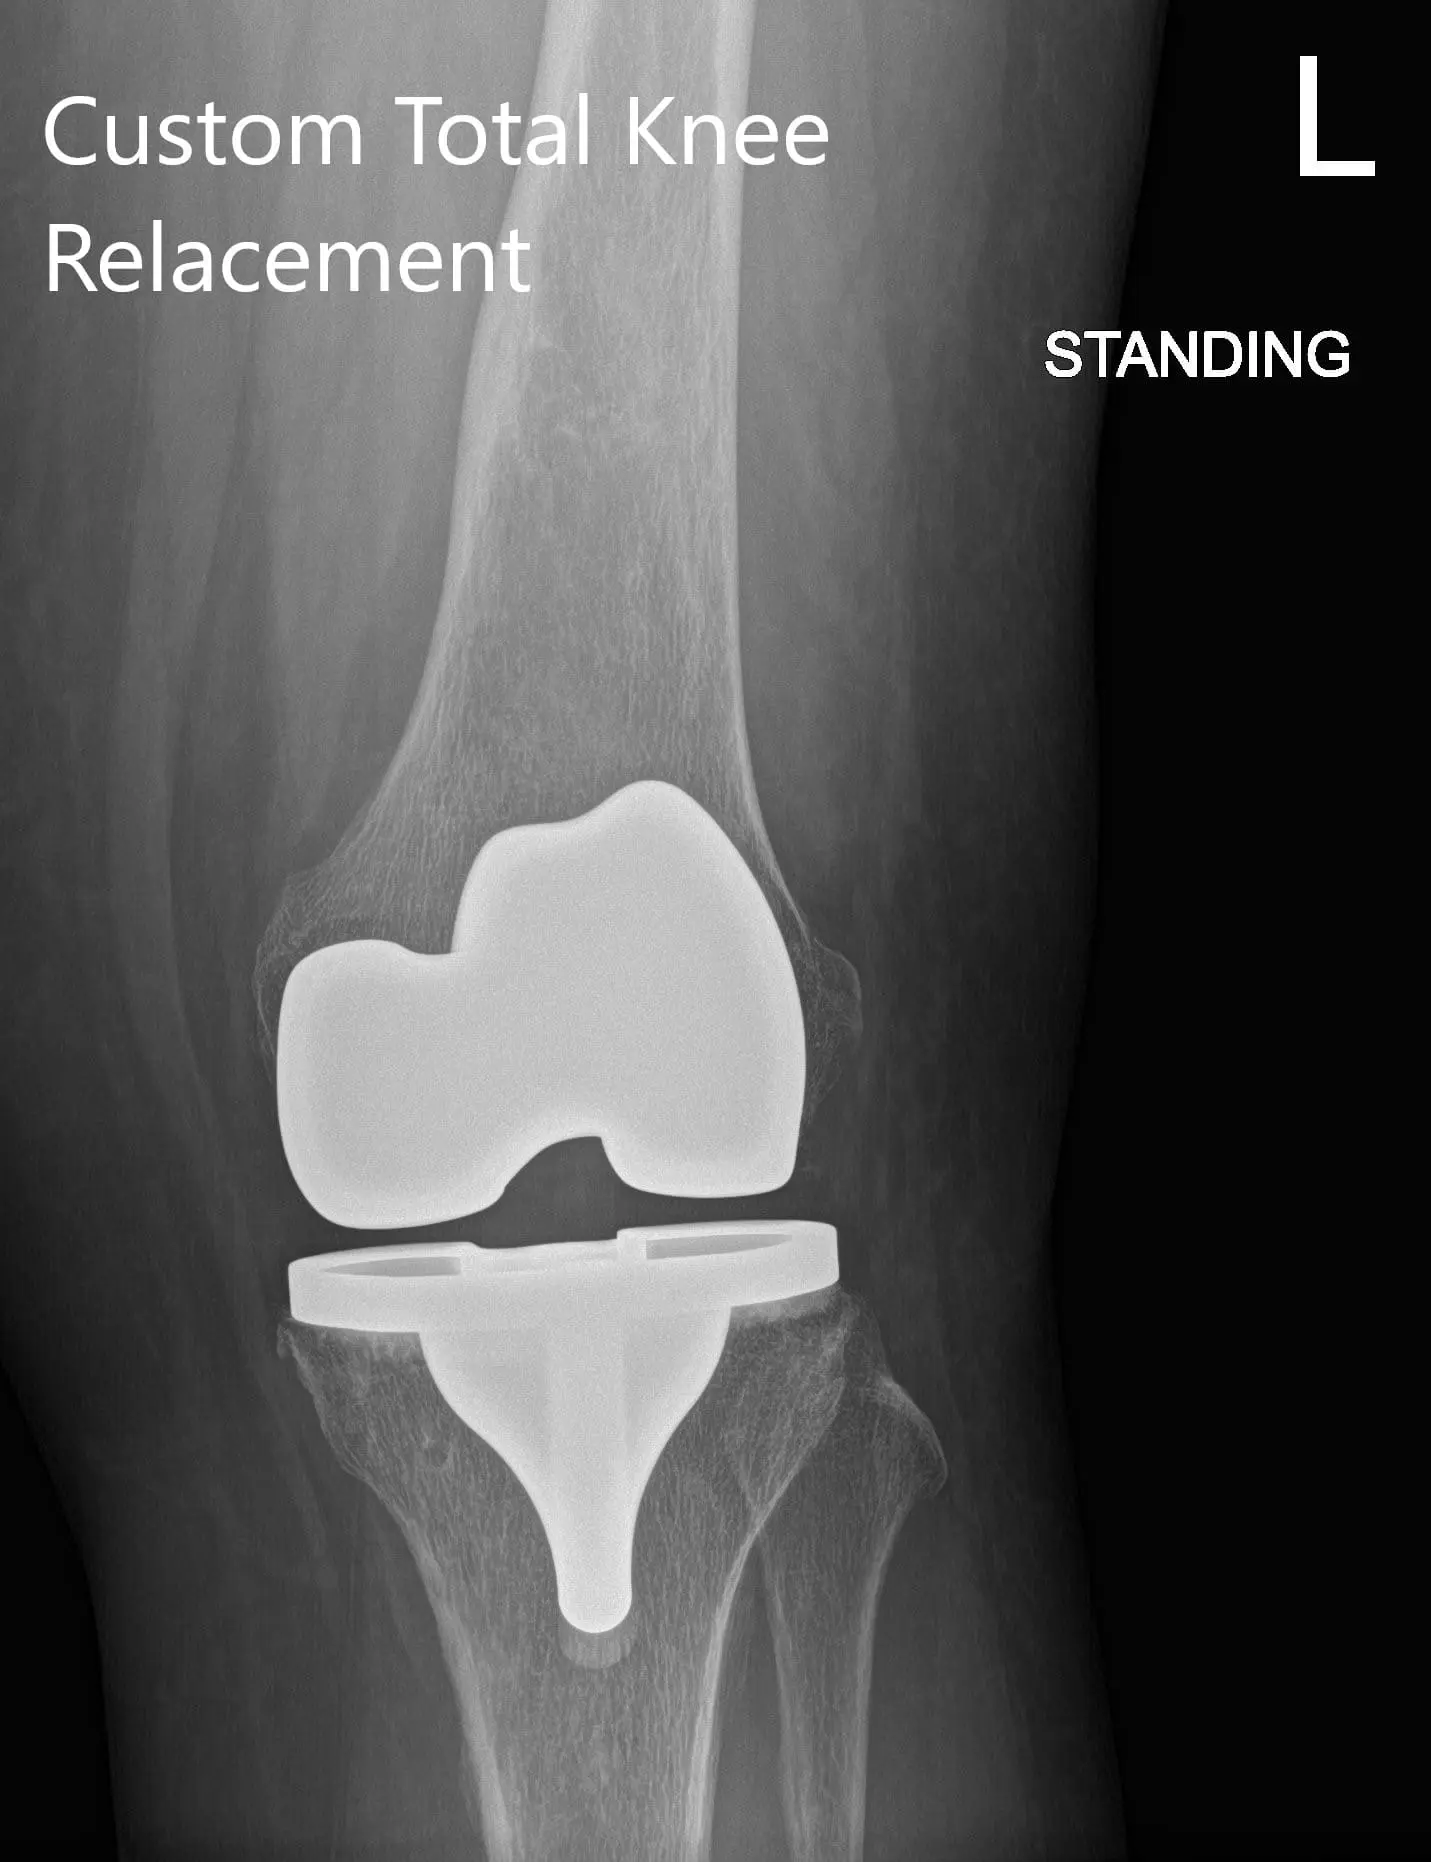

Postoperative X-ray showing AP and lateral view of the left knee

Postoperatively, he was walking the same day and was started on aspirin for deep vein thrombosis prophylaxis. He had excellent pain relief with multimodal pain management. The patient was subsequently seen for sterile dressing change and his wound was found to be dry, clean and intact. Staples were removed and the patient demonstrated a full range of motion.

The patient was extremely happy with the outcome and after 3 months he successfully concluded his physical therapy. He had since returned to playing tennis and volunteering at a children’s hospital. He was able to resume his work as a nurse and was active without any pain or stiffness. The patient follows up as needed.